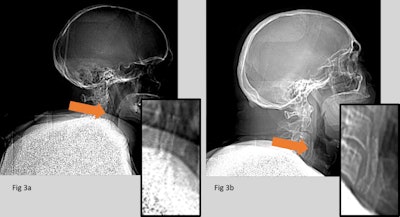

(Left) CT scout image contains the missed carotid stent. (Right) Carotid stent correctly identified. The carotid stent in Fig. 3a, although visible, is partially obscured by superimposed anatomy. This case shows implants can be difficult to identify, and both image quality and the experience of staff can play a role.Both readers also missed a hidden frenum piercing, which was present within a projection with multiple implants. The small metallic foreign body was correctly identified, despite being superimposed over the dense bone of the skull base.